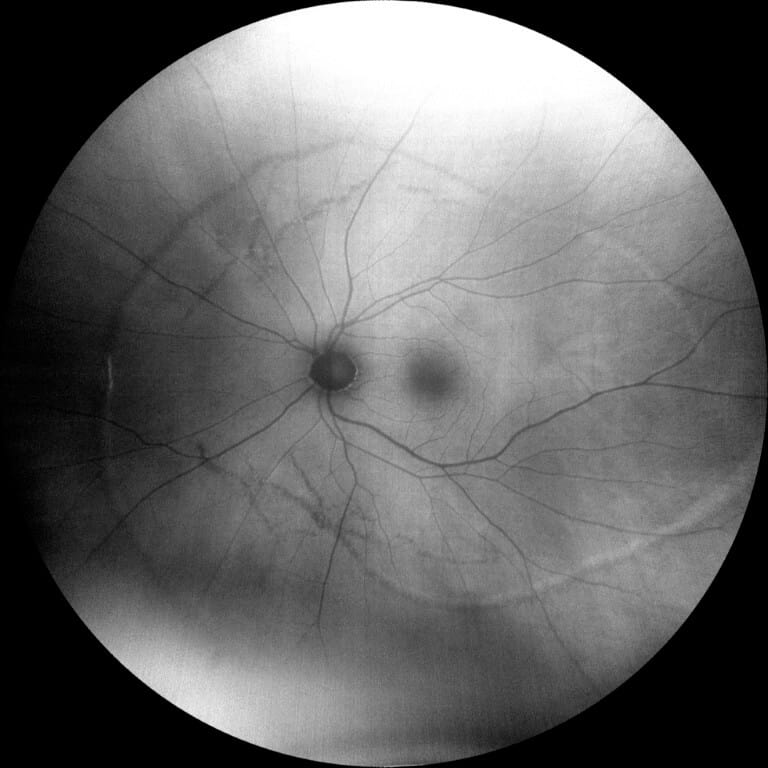

A 67-year-old male presented for a routine eye exam. The patient reported no visual complaints and denied ocular pain, photopsia, new floaters, metamorphopsia, or diplopia. His medical history included obesity and no history of systemic inflammatory or infectious disease. He denied any history of ocular trauma or surgery. The patient’s uncorrected and corrected visual acuity was 20/20 in each eye. Extraocular muscles, confrontation fields and pupils were normal. Slit-lamp examination for the right and left eye was unremarkable. Following dilation with 1% tropicamide and 2.5% phenylephrine, funduscopic examination was performed. The optic discs were normal with a cup-to-disc ratio 0.30 round. The macula in each eye was flat with normal OCT (Figure 1-2). However, examination of both eyes revealed multiple, curvilinear, pigmented chorioretinal lines originating in the posterior pole and extending outward in a distinct spiral pattern toward the midperiphery. Color fundus photographs as well as fundus autofluorescence images were obtained (Figures 3-6). There was also a punched-out chorioretinal lesion nasal to the optic nerve head in the right eye (Figure 3,5).

Figure 6: Fundus autofluorescence of the left eye showed mixed areas of hypo- and hyperautofluorescent lines corresponding to RPE atrophy and hyperplasia.